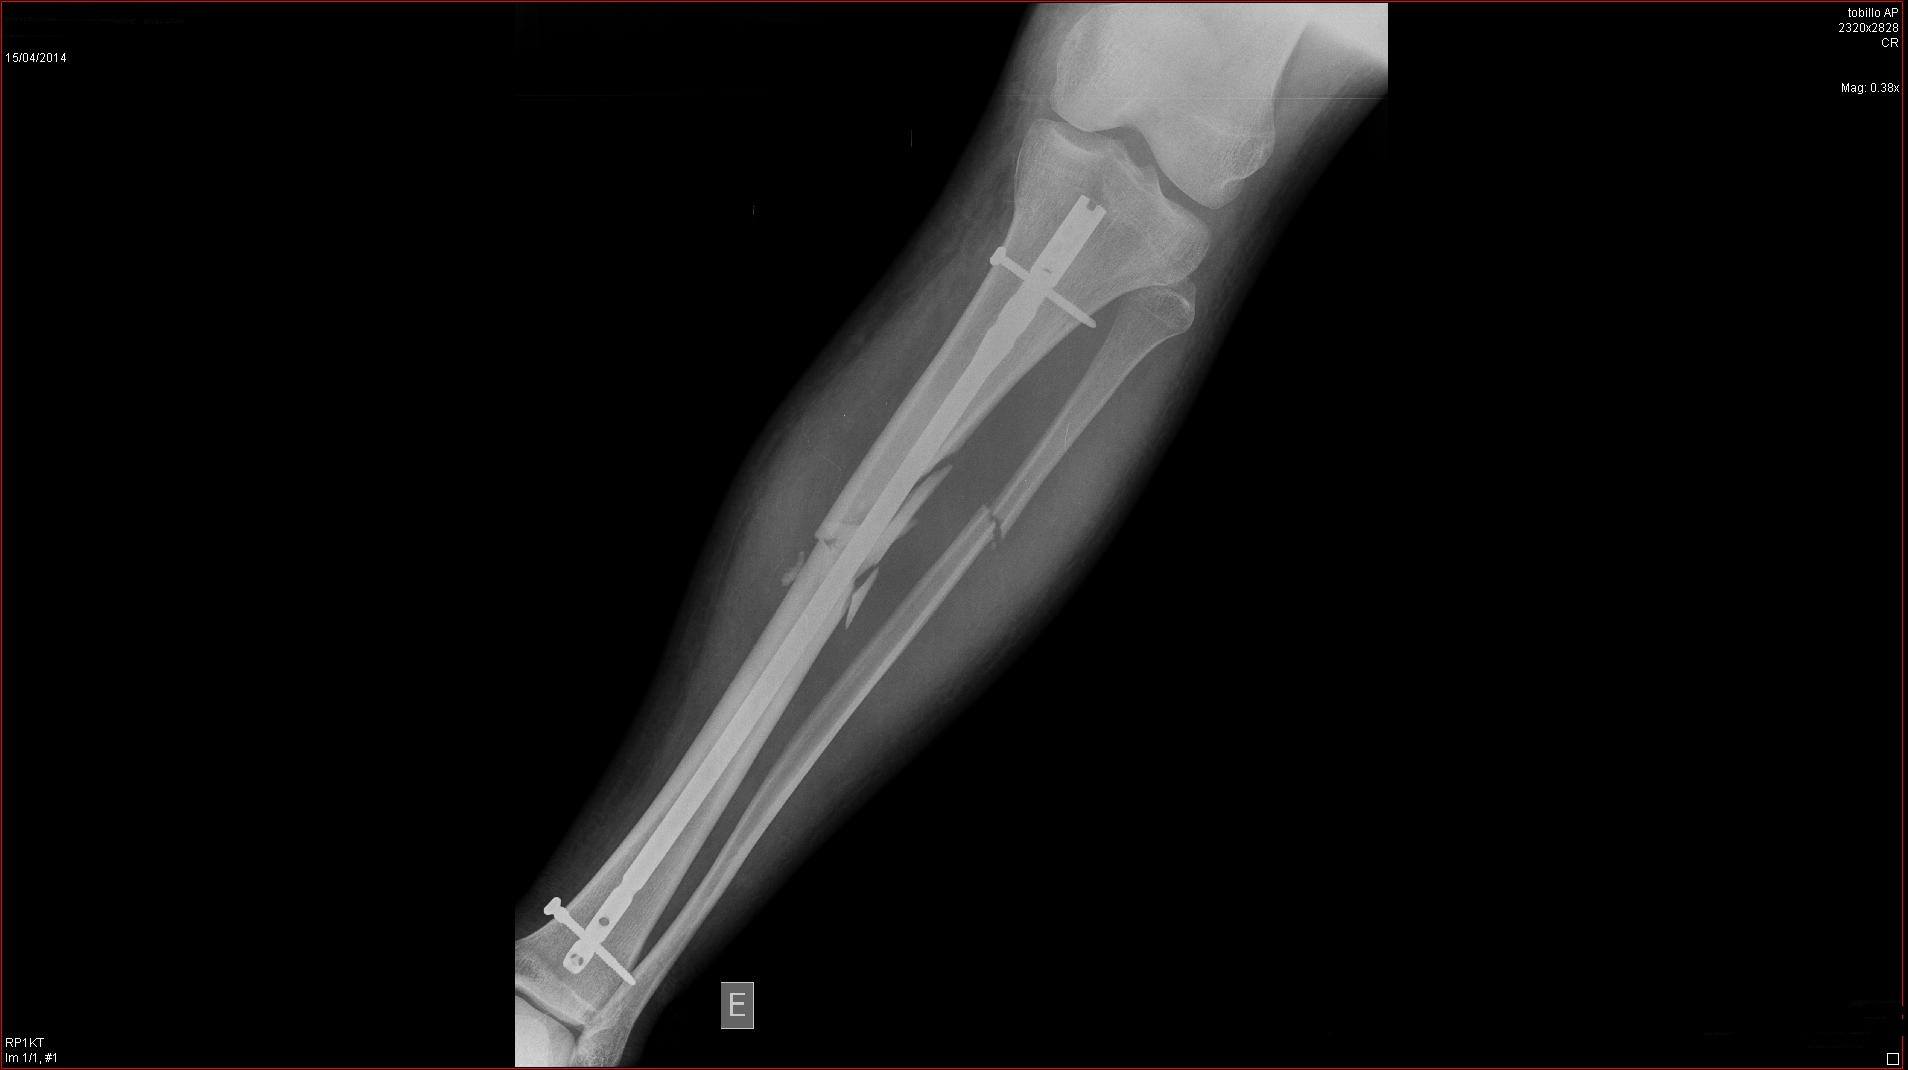

Ahora mismo es lo unico que puedo hacer, recordar los buenos momento, tengo la tibia y peroné rodas y estilladas desde hace 4 meses, más lo que me falta para volver a caminar, así que toca esperar y tener paciencia :(

Yo llevo 4 meses en el dique seco, me quedo asi la pata despues de ser atropellado en un paso de peatones por una moto que adelanto a un coche que me estaba cediendo el paso (Que aun tiene más delito!)

Despues de 4 meses aun lo tengo así

Pero como el mono es tan fuerte, ya empiezo a darle a pata coja! Ya que ni tengo ni la tibia ni peroné pegados, apenas puedo mantenerme de pie con esta pierna :(

Yo este año me quedado sin hacer el Campeonato Challenger Master30 de Catalunya, ni el campeonato de larga distancia, ni las classicas de verano, y lo que queria hacer con más ilusión de todo, el campeonato de Catalunya de CicloCross :( Finalmente este lunes me volvieron a operar despues de los contratiempos de la semana pasada, me recuperación aun sera más lenta de lo esperado :(